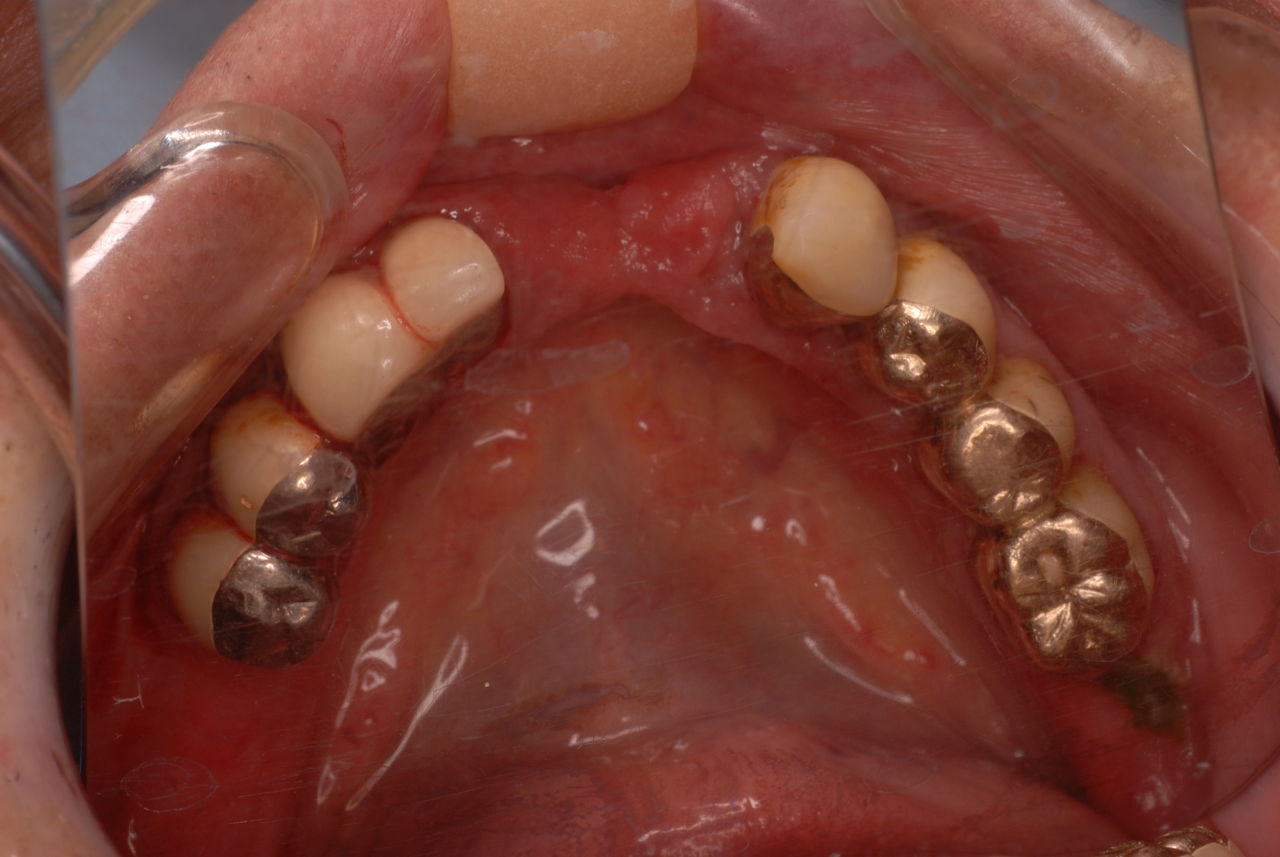

下の歯は数本存在しますが、全て虫歯と歯周病に犯されていました。

食べカスまみれで歯周病に罹患しています。